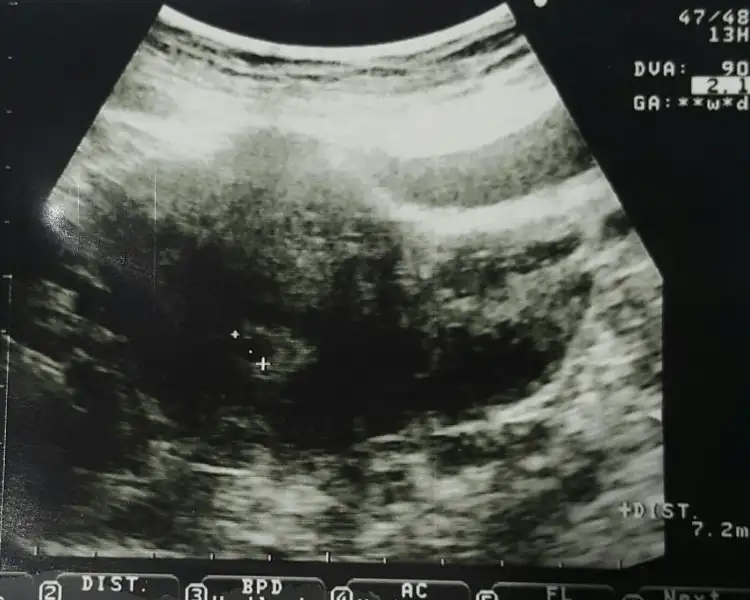

Tescillendi hamileliğin ne güzel. Pazartesi gidecektim normal şartlarda ben de.. Soracağım sorular var doktora, ama bir hafta daha bekleyeceğim.Biz bugün doktora gittik kesemizi gördük darısı başınızaEki Görüntüle 1975585

Ay maşallah maşallahBiz bugün doktora gittik kesemizi gördük darısı başınızaEki Görüntüle 1975585

Biz bugün doktora gittik kesemizi gördük darısı başınızaEki Görüntüle 1975585

Hayirli olsun vajinal mi bakti acaba karindan miBiz bugün doktora gittik kesemizi gördük darısı başınızaEki Görüntüle 1975585